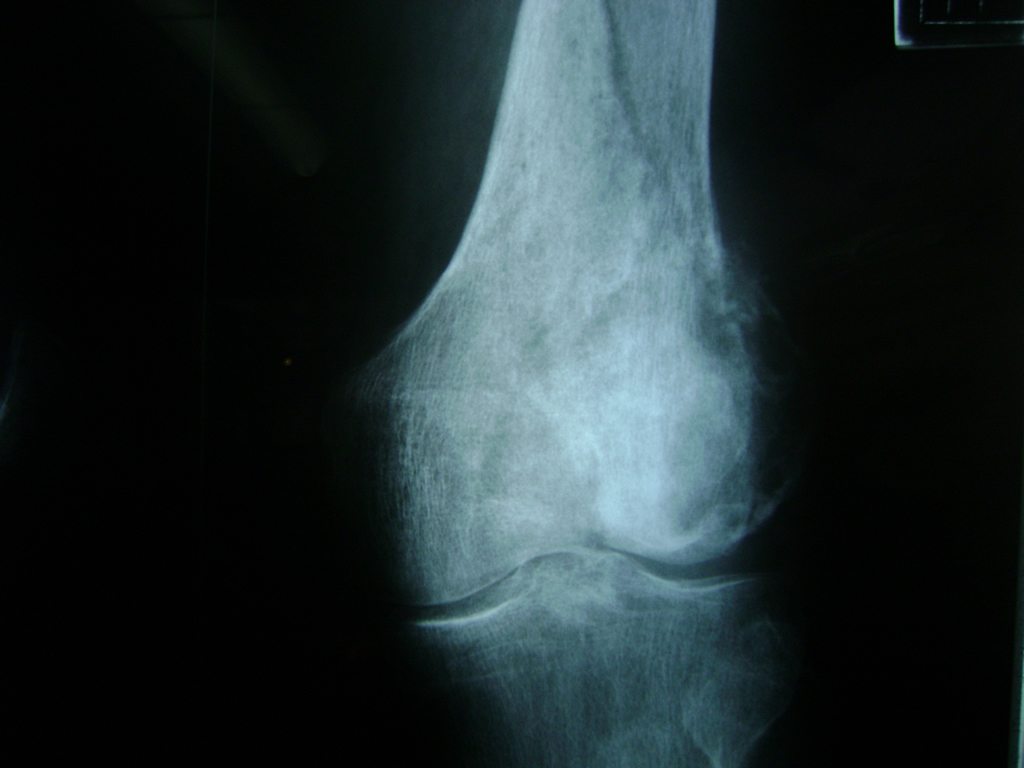

Cirugía de Fémur - Rodilla

La artroscopia de rodilla es un cirugía en el cual la estructura interna de la articulación es examinada ya sea para realizar un diagnostico o para realizar un tratamiento, este procedimiento se realiza utilizando un instrumento parecido a un pequeño tubo llamado artroscopio.